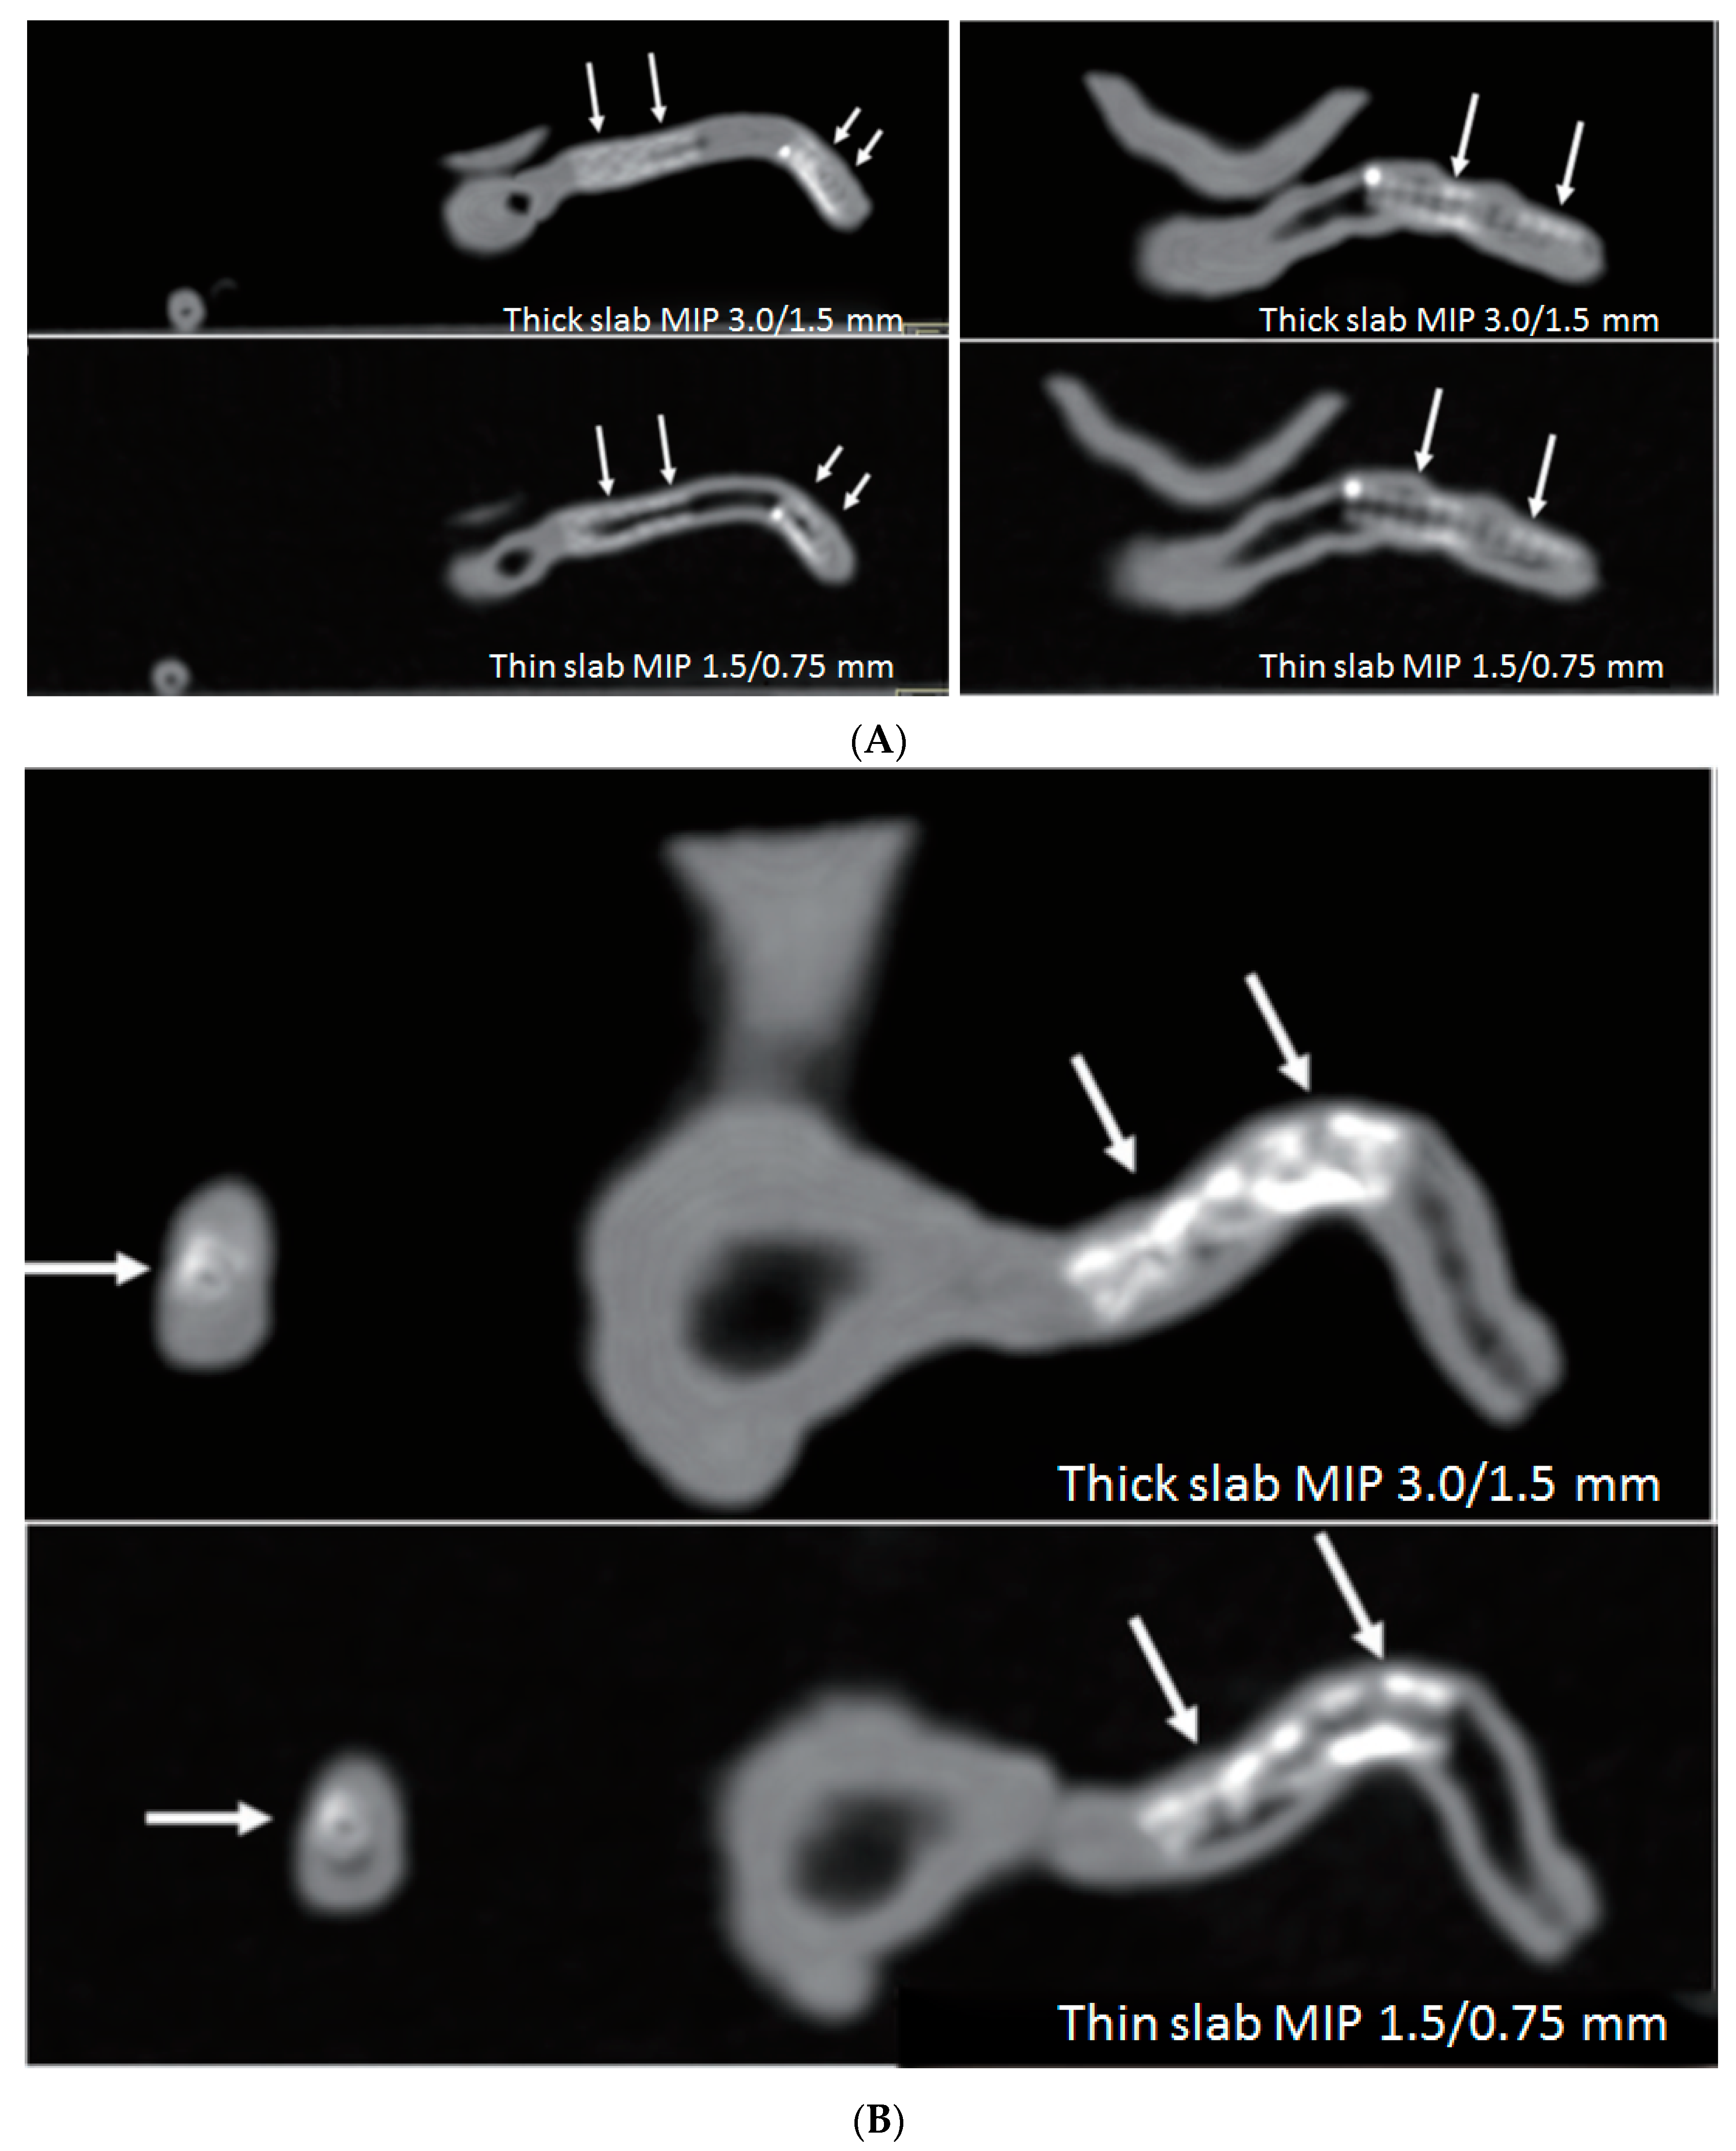

- Sun, Z.; Ng, C.K.; Squelch, A. Synchrotron radiation computed tomography assessment of calcified plaques and coronary stenosis with different slice thicknesses and beam energies on 3D printed coronary models. Quant. Imaging Med. Surg. 2019, 9, 6–22. [Google Scholar] [CrossRef] [PubMed]

- Sun, Z. 3D printed coronary models offer new opportunities for developing optimal coronary CT angiography protocols in imaging coronary stents. Quant. Imaging Med. Surg. 2019, 9, 1350–1355. [Google Scholar] [CrossRef] [PubMed]

- Sun, Z.; Jansen, S. Personalized 3D printed coronary models in coronary stenting. Quant. Imaging Med. Surg. 2019, 9, 1356–1367. [Google Scholar] [CrossRef] [PubMed]

- Aldosari, S.; Jansen, S.; Sun, Z. Optimization of computed tomography pulmonary angiography protocols using 3D printed model with simulation of pulmonary embolism. Quant. Imaging Med. Surg. 2019, 9, 53–62. [Google Scholar] [CrossRef] [PubMed]

- Aldosari, S.; Jansen, S.; Sun, Z. Patient-specific 3D printed pulmonary artery model with simulation of peripheral pulmonary embolism for developing optimal computed tomography pulmonary angiography protocols. Quant. Imaging Med. Surg. 2019, 9, 75–85. [Google Scholar] [CrossRef] [PubMed]